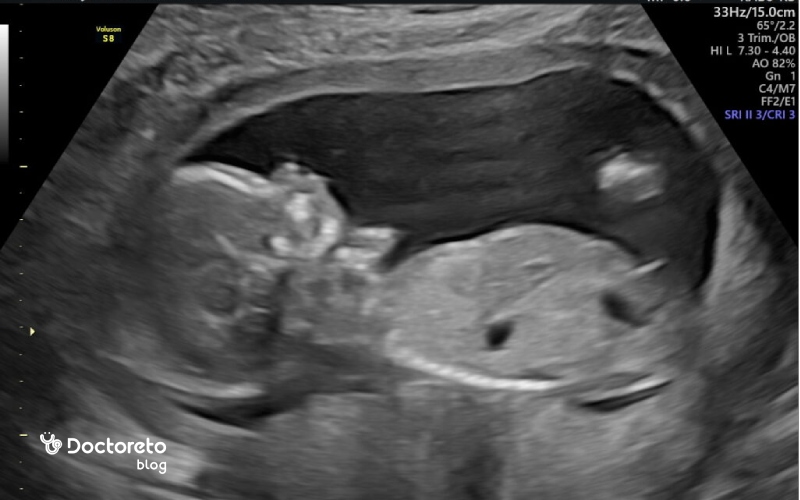

هفته شانزدهم بارداری زمانی است که بسیاری از نشانههای آزاردهنده سهماهه نخست فروکش کرده و احساس تعادل جسمی و ذهنی پررنگتر میشود. شکم بهتدریج گردتر میشود و برخی مادران، بهویژه در بارداریهای غیرنخست، نخستین قلقلکهای حرکتی جنین را درک میکنند. درون رحم، استخوانها سفتتر، عضلات نیرومندتر و چهره جنین کاملتر میشود؛ همزمان، مسیرهای حسی در حال شکلگیریاند و پاسخ به صداها امکانپذیر میشود. در تصویربرداری این هفته، رشد طولی و ارزیابی ضربان قلب و موقعیت جفت مورد توجه قرار میگیرد و دادههای آن با نتایج غربالگری سهماهه دوم کنار هم گذاشته میشود تا تصویری منسجم از روند تکاملی شکل گیرد. در این مطلب از دکترتو، با هفته شانزدهم بارداری آشنا میشوید.

در هفته شانزدهم بارداری، جنین ظاهری شبیه یک نوزاد کوچک و کاملتر پیدا کرده است. او حدود ۱۱ تا ۱۲ سانتیمتر طول و حدود ۱۰۰ گرم وزن دارد. سر جنین هنوز نسبتاً بزرگتر از بدن است اما بهتدریج تناسب اندامها در حال شکلگیری است. دستها و پاها کشیدهتر شدهاند، انگشتان بهطور کامل تفکیک شده و ناخنهای ظریفی در حال رشدند. پوست هنوز نازک و نیمهشفاف است و از زیر آن رگهای خونی دیده میشوند. روی بدن جنین موهای نازکی به نام لانگو (Lanugo) شروع به رشد کرده و صورت او حالا با چشمها، گوشها، بینی و چانه مشخصتر شده است. در سونوگرافی این هفته میتوان حرکات، مکیدن انگشت یا حتی چرخش بدن جنین را مشاهده کرد که نشانه رشد طبیعی اوست.

در هفته شانزدهم بارداری، جنین بهطور فعال در رحم حرکت میکند و عضلاتش آنقدر رشد کردهاند که میتواند دستها و پاهای خود را خم و راست کند، بچرخد و حتی انگشتش را بمکد. بااینحال، این حرکات هنوز بسیار ظریفاند و ممکن است همه مادران نتوانند آن را احساس کنند. معمولاً مادرانی که بارداری دوم یا سوم خود را تجربه میکنند، زودتر از دیگران متوجه این حرکات میشوند. در سونوگرافی هفته شانزدهم، میتوان تکانها، چرخشها و حرکات آرام جنین را مشاهده کرد. این حرکات نشانه رشد سالم سیستم عصبی و عضلانی اوست و در هفتههای آینده، قویتر و قابلاحساستر خواهند شد.

در هفته شانزدهم بارداری، سونوگرافی نقش مهمی در بررسی رشد و سلامت جنین دارد. در این مرحله، پزشک میتواند اندازه جنین، ضربان قلب، حرکات، وضعیت جفت و میزان مایع آمنیوتیک را مشاهده کند و از رشد طبیعی اندامهایی مانند مغز، قلب، کلیهها و ستون فقرات اطمینان یابد. در بسیاری از موارد، جنسیت جنین نیز در این هفته قابل تشخیص است، هرچند به وضعیت قرارگیری او بستگی دارد. این سونوگرافی معمولاً بخشی از غربالگری سهماهه دوم است و به شناسایی زودهنگام ناهنجاریهای احتمالی و اطمینان از روند طبیعی بارداری کمک میکند.